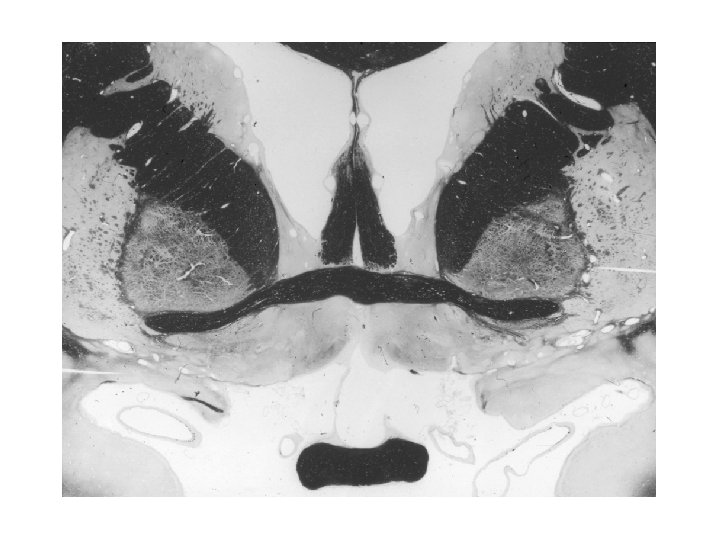

Area postrema Az ún. circumventriculáris szervek közé tartozik, melyek az agykamrák falánál jellegzetes sejtcsoportokat alkotnak, területükön nincs vér-agy gát. Mint ilyen, az area postrema, mely emberben az obexnél a IV. kamra két oldalán helyezkedik el, a nyúltvelő „nyitott kapujának” tekinthető, melynek erein át a nyúltvelő viszceroszenzoros központja (nucleus tractus solitarii) humorális afferentációt kap. Az area postremát a n. vagus idegzi be. Sokáig „hányás központ”-ként volt ismeretes.

Nucleus tractus solitarii (Nucleus of the solitary tract – NTS) Primer viszceroszenzoros mag a nyúltagy dorsalis részében. Viszceroszenzoros általános és viszceroszenzoros speciális (ízérző) rostok kapcsolódnak itt át. Rostokat kap a gerincvelőből is (tractus spinosolitarius). Felszálló viszceroszenzoros rostjai az amygdalában és a hypothalamusban, ízérző rostjai az insuláris kéregben végződnek. Az NTS érző neuronjai a vagus viszceromotoros neuronjaival (nucleus motorius dorsalis vagi) az autonóm szabályozó reflexívek részei. Artériás ellátása egyedi a dorsális medullában, a posterior inferior cerebelláris artéria látja el az area postremán keresztül. Az erek jelentős részén nincs vér-agy gát, így az NTS a nervus vaguson és a gerincvelőn kívül jelentős humorális afferentációt is kap.